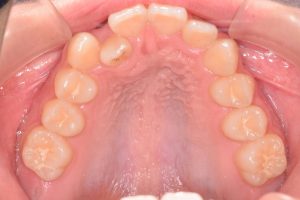

上あご

0000000006

0000000026

0000000077